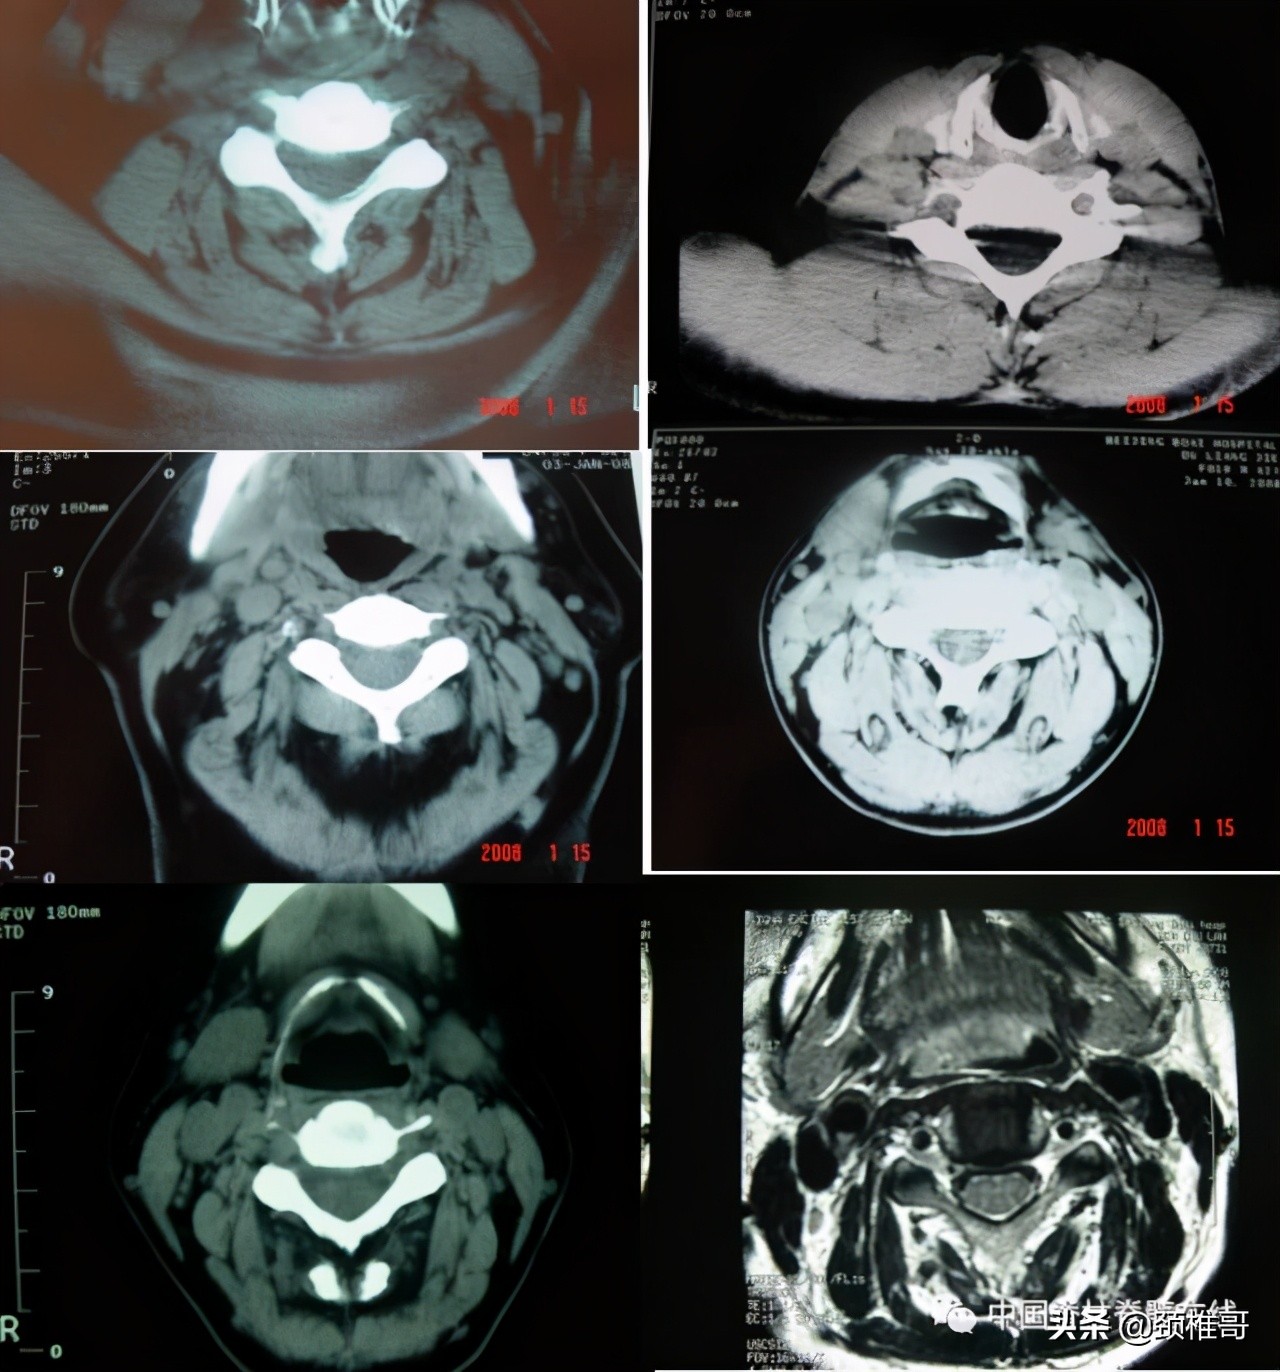

颈椎病患者与正常人(右上第一第二图)颈椎周围肌肉退变情况对比

另外一个例子,这是一个头晕8年的病人,他的颈椎核磁共振显示,颈椎3-6各个节段之间的椎间盘退变膨出,局部有一些骨质增生,但没有明显的神经受压,横断面扫描显示颈椎周围肌肉有严重的退变表现;在X线检查时发现,棘突排列顺序不佳,颈4/5椎体之间有台阶,颈椎3-7各个节段之间夹角增大,都超过了11度;过屈位显示颈2-4椎出现了双边征,是旋转不稳的表现。这个病人的椎间盘虽然已经出现了退变、膨出,并发生了骨质增生,对硬膜囊产生了轻度压迫。但是其主要问题是椎间盘退变吗?不对,其主要问题还是多节段的椎间不稳,既有夹角增大,又有台阶,还有旋转。导致此病人头晕的主要原因还是肌肉和韧带的控制能力的下降所导致的。

正位显示椎体序列不佳、侧位显示颈椎4/5之间台阶状改变

过伸过屈侧位X线片显示多节段颈椎不稳

在椎间盘膨出、颈椎不稳基础上发生的代偿性增生

颈椎周围肌肉退变在颈椎病的发生发张过程中发挥着极其重要的作用